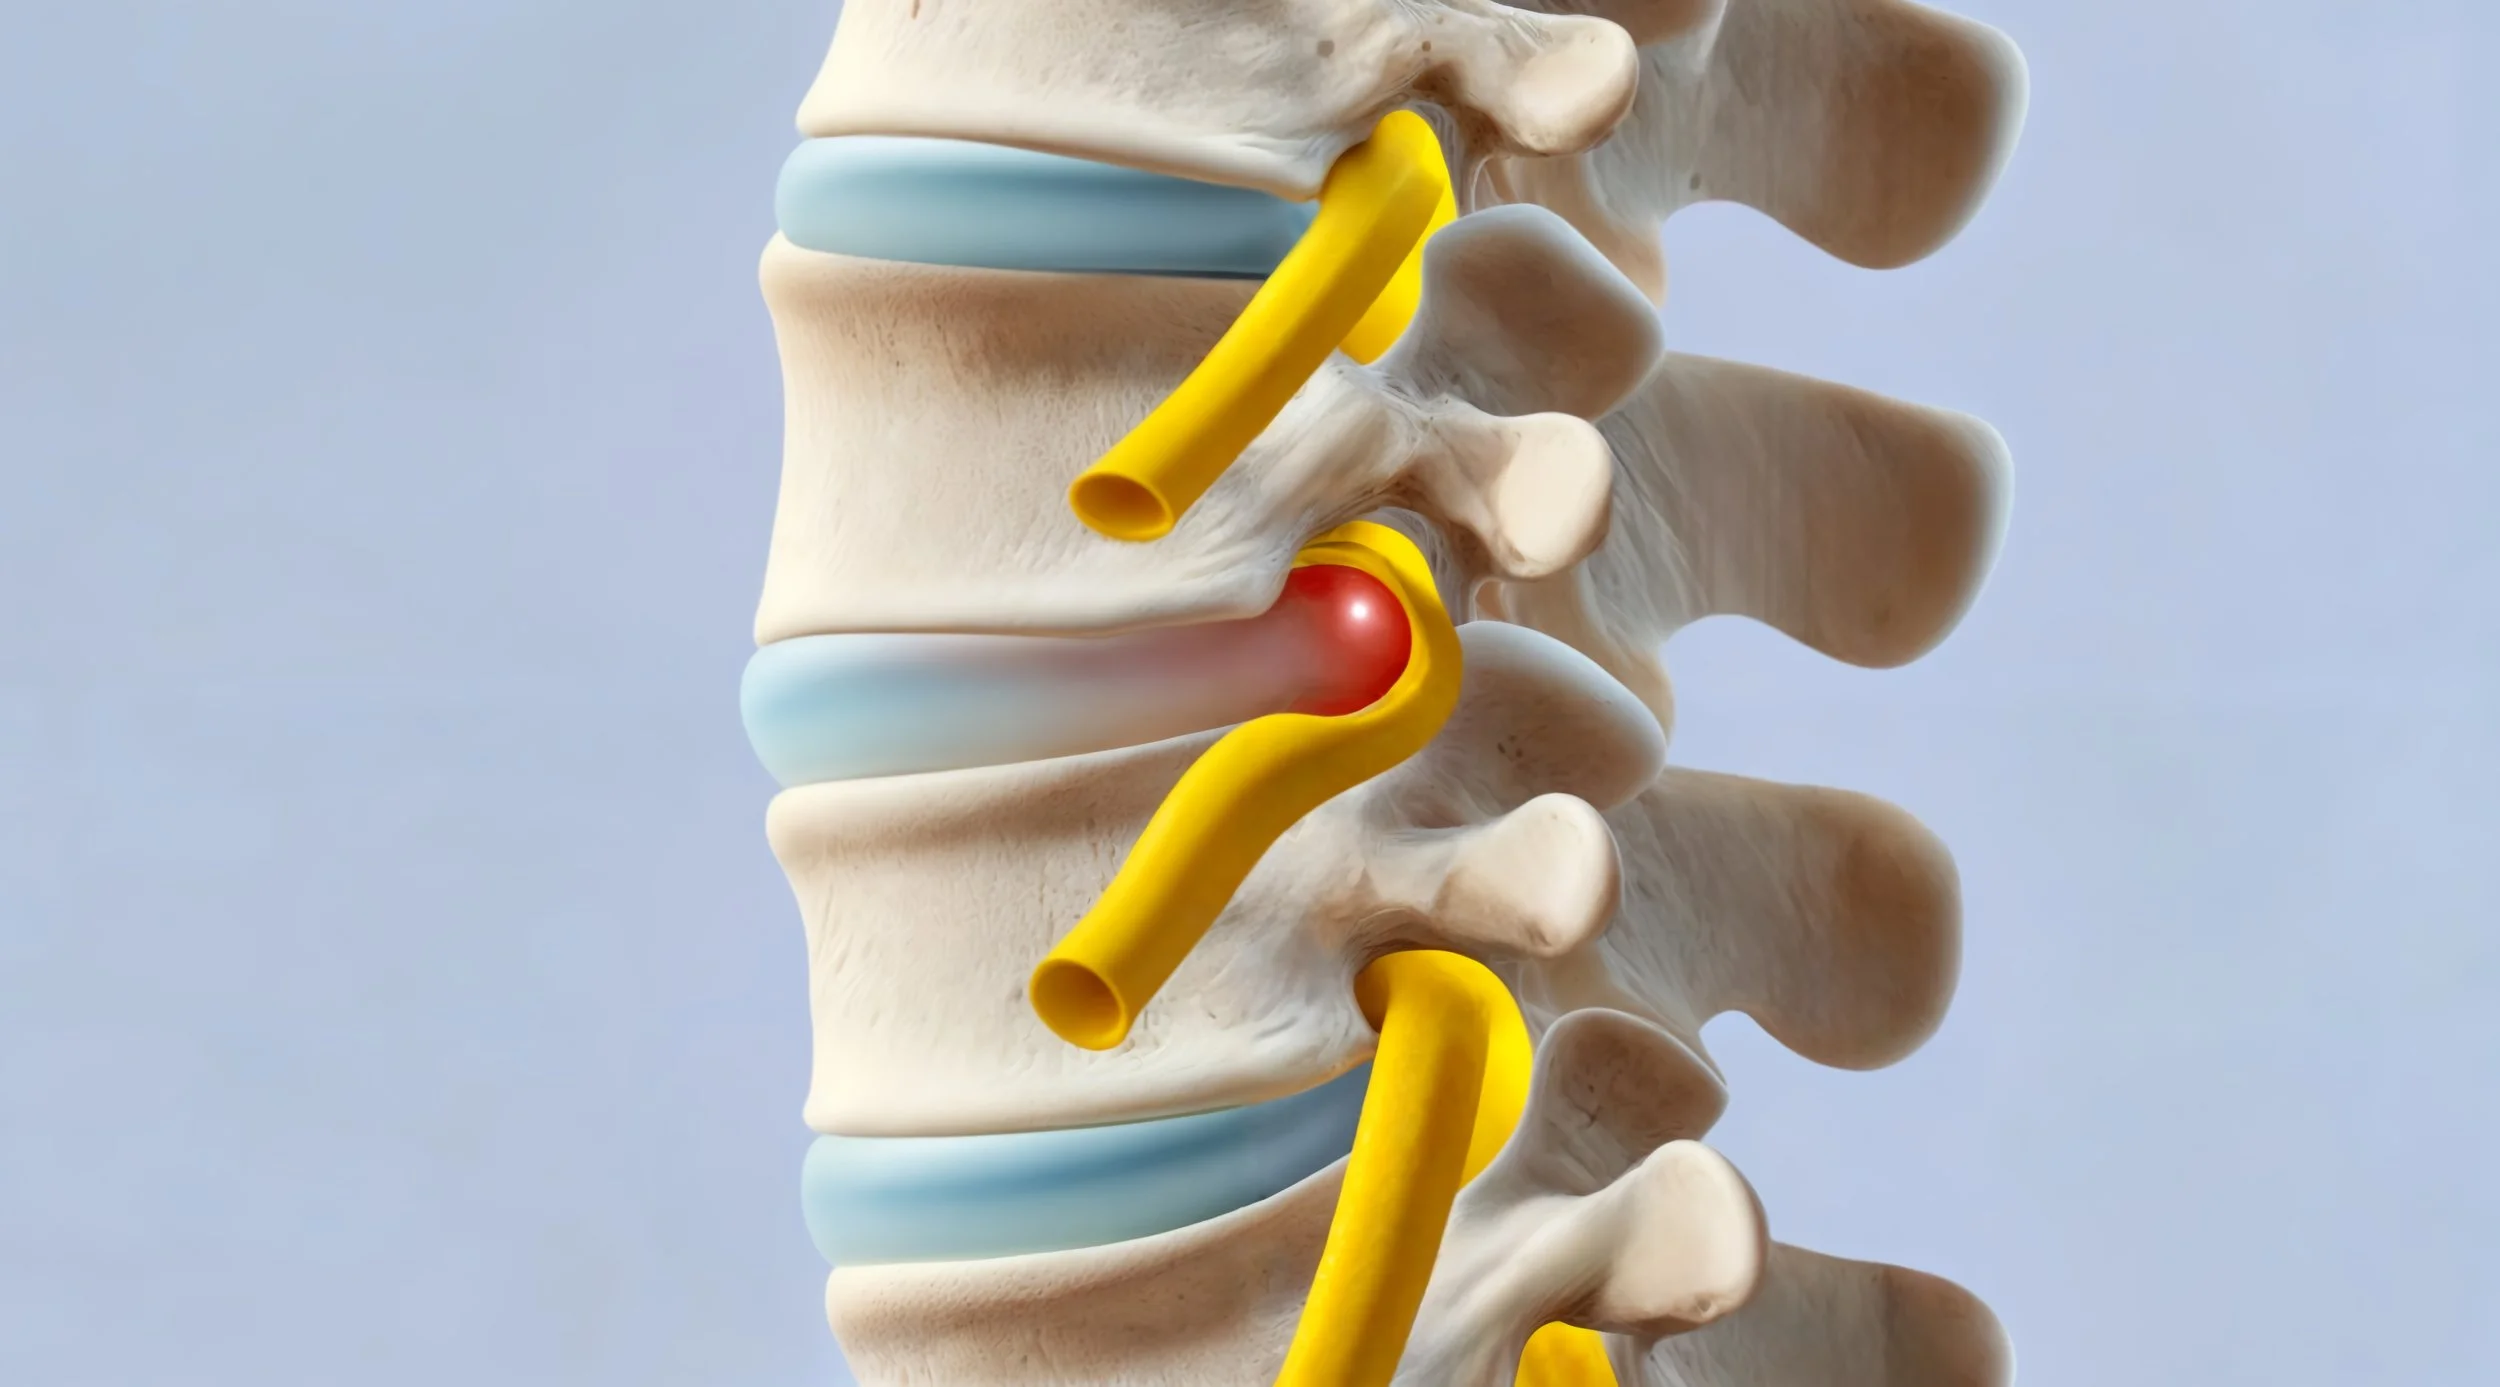

Et prolaps, også kalt skiveprolaps eller diskprolaps, oppstår når en av mellomvirvelskivene i ryggraden blir skadet slik at den myke kjernen i skiven presses utover. Dette kan føre til irritasjon eller trykk på en nerve. Mellomvirvelskivene fungerer som støtdempere mellom virvlene i ryggen. Når en skive svekkes eller sprekker, kan noe av innholdet presses ut og påvirke nerverøtter i ryggraden.

Prolaps forekommer oftest i:

• korsryggen (lumbal prolaps)

• nakken (cervikal prolaps)